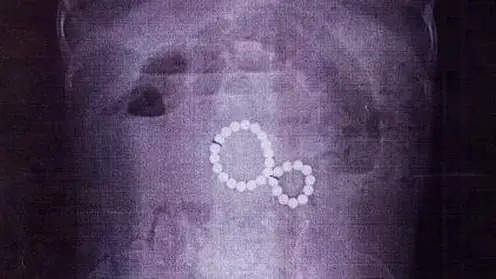

В Красноярске смогут диагностировать первые признаки рака — в ФМБА заработал аппарат ПЭТ-КТ

Ранее единственный в городе пробор сломался, а красноярцы с онкологией ездили на диагностику в другие регионы